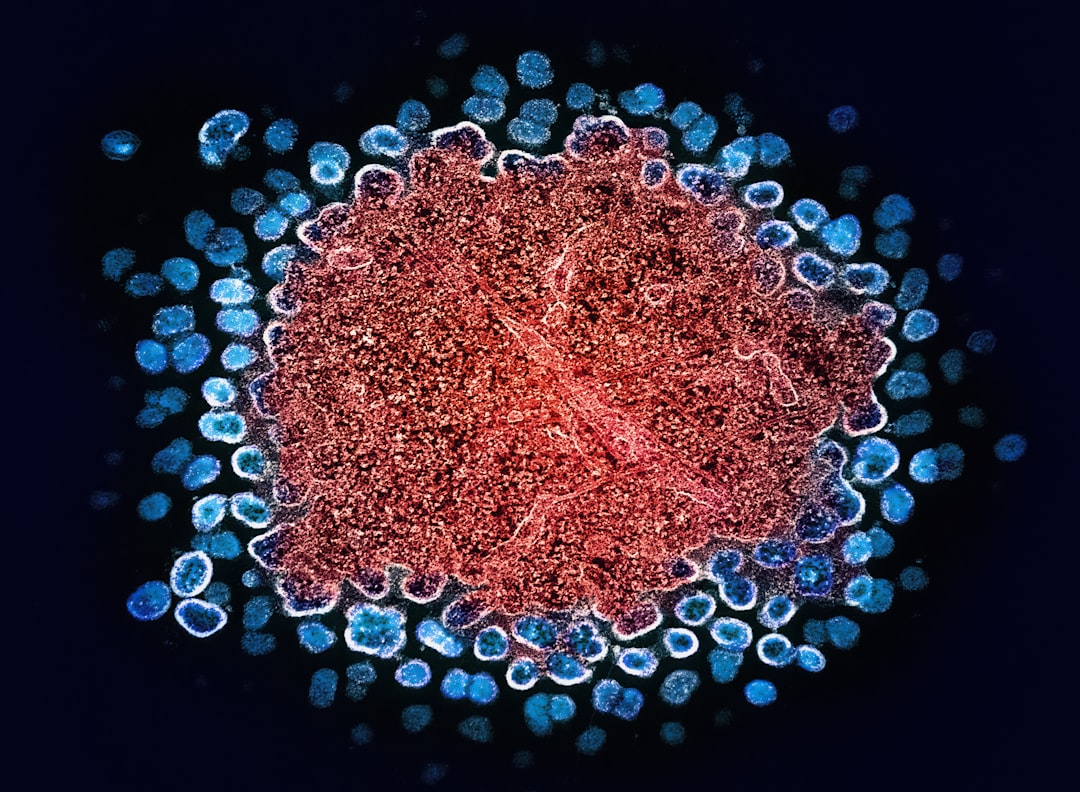

이 치료 기법은 줄기세포를 활용해 신경 세포를 재생하는 것입니다. 줄기세포는 다양한 세포로 분화할 수 있는 능력을 가지고 있어, 손상된 세포를 대체할 수 있는 가능성을 지니고 있습니다. 따라서 파킨슨 줄기세포 치료는 황금 같은 기회를 제공할 수 있는 혁신적인 접근법으로 주목받고 있습니다.

줄기세포가 신경 세포로 변해 손상된 뉴런을 대체하는 과정은 복잡합니다. 이 과정은 여러 단계를 거쳐 진행되며, 줄기세포가 적절한 환경에서 융합하고 기능을 할 수 있는지에 대한 연구가 필요합니다. 또한, 이 치료의 장기 효과에 대한 연구도 진행되고 있으며, 이를 통해 환자들에게 보다 안전하고 효과적인 치료법을 제공할 수 있을 것입니다.

주로 환자의 줄기세포를 추출하여 실험실에서 성장시킨 후, 이를 환자의 손상된 부위에 주입하여 신경 세포를 재생하는 방식으로 진행됩니다.